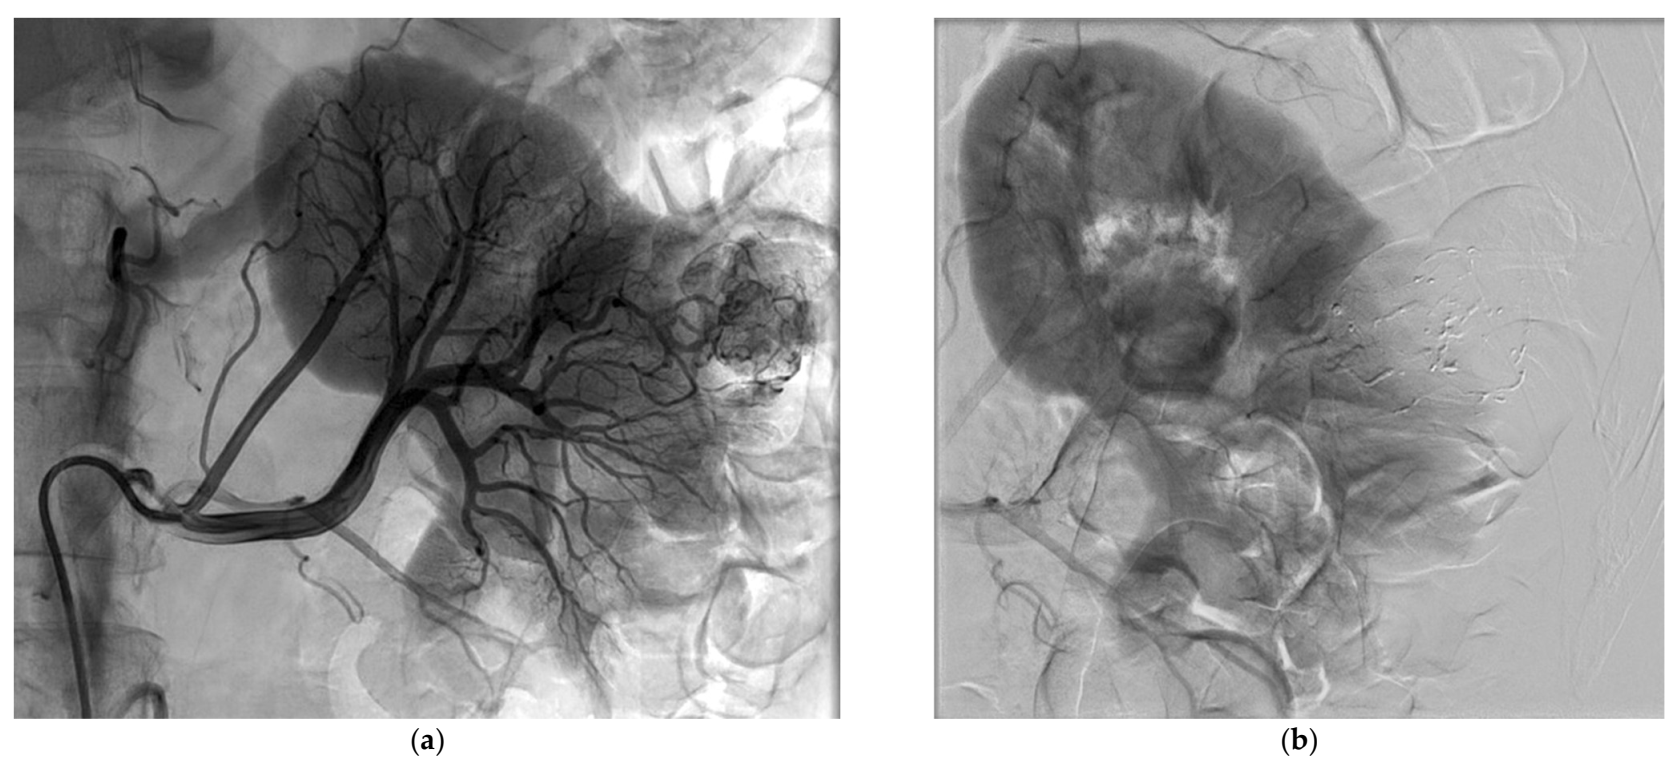

Successful SAE was achieved for all patients, but complete SAE in 11 patients (57.9%). Complete SAE could not be achieved in the remaining eight patients since it would have led to an unacceptable loss of surrounding healthy tissue. However, for cases with incomplete embolization, devascularization was obtained for most of the tumor volume, always greater than 50% on control angiogram. The most used NBCA/Lipiodol® ratio range was 1/3 to 1/5, in 18 patients. Mean procedure time was 93 ± 43 min and mean fluoroscopy time was 18 ± 11 min. The mean DSP for the SAE procedure was 120.7 ± 68.7 Gy.cm2. The mean volume of injected contrast medium was 119 ± 50 mL. The mean NRS pain score was 0.89 ± 1.52 after SAE. Table 3 lists the main characteristics of the SAE procedure. Figure 1 and Figure 2 show examples of SAE of renal cell carcinoma before PCA.

Figure 2.

Selective arterial embolization (SAE) procedure using NBCA/Lipiodol® mixture performed before percutaneous cryoablation of a renal cell carcinoma of the upper pole of the left kidney. (a,b) Angiogram showed hypervascularrenal malignancy. (c) Selective angiogram after embolization of a feeding artery of the tumor showing another feeding artery with residual tumor blush. (d) Control angiogram showing the occlusion of the two major feeding arteries after embolization with a small residual tumor blush (white arrow).